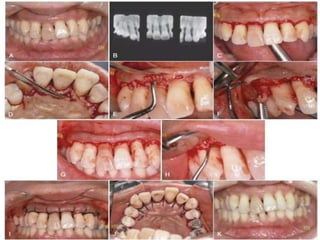

UNDISPLACED FLAP

▸ Most frequently performed type of periodontal surgery

▸ It differs from the modified Widman flap in that the

soft-tissue pocket wall is removed with the initial

incision; thus, it may be considered an “internal bevel

gingivectomy”

▸ The undisplaced flap and the gingivectomy are the two

techniques that surgically remove the pocket wall

▸ Step 1: The pockets are measured with the periodontal

probe and a bleeding point is produced on the outer

surface of the gingiva to mark the pocket bottom

▸ Step 2: The initial or internal bevel incision is made after

scalloping the bleeding marks on the gingiva. The

incision is usually carried to a point apical to the

alveolar crest, depending on the thickness of the tissue.

The thicker the tissue is, the more apical the ending

point of the incision. In addition, thinning of the flap

should be performed with the initial incision, because it

is easier to accomplish at this time than it is later with a

loose, reflected flap that is difficult to manage.

▸ Step 3: The second or crevicular incision is made from

the bottom of the pocket to the bone to detach the

connective tissue from the bone

▸ Step 4: The flap is reflected with a periosteal elevator

(blunt dissection) from the internal bevel incision.

Usually there is no need for vertical incisions, because

the flap is not displaced apically

▸ Step 5: The third or interdental incision is made with an

interdental knife to separate the connective tissue from

the bone

▸ Step 6: The triangular wedge of tissue created by the

three incisions is removed with a curette

▸ Step 7: The area is debrided to remove all tissue tags and

granulation tissue with the use of sharp curettes

▸ Step 8: After the necessary scaling and root planing, the

flap edge should rest on the root–bone junction. If this

is not the case as a result of the improper location of

the initial incision or the unexpected need for osseous

surgery, the edge of the flap is scalloped again and

trimmed to allow the flap edge to end at the root–bone

junction

▸ Step 9: A continuous sling suture is used to secure the

facial and lingual or palatal flaps. This type of suture,

which makes use of the tooth as an anchor, is

advantageous to position and hold the flap edges at

the root–bone junction. The area is covered with a

periodontal pack.